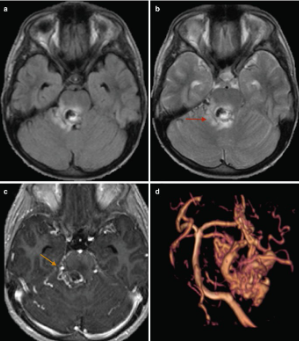

Figure 1. Citra MRI otak pasien dengan trigeminal neuralgia menunjukkan area kompresi pembuluh darah kecil pada saraf trigeminus.